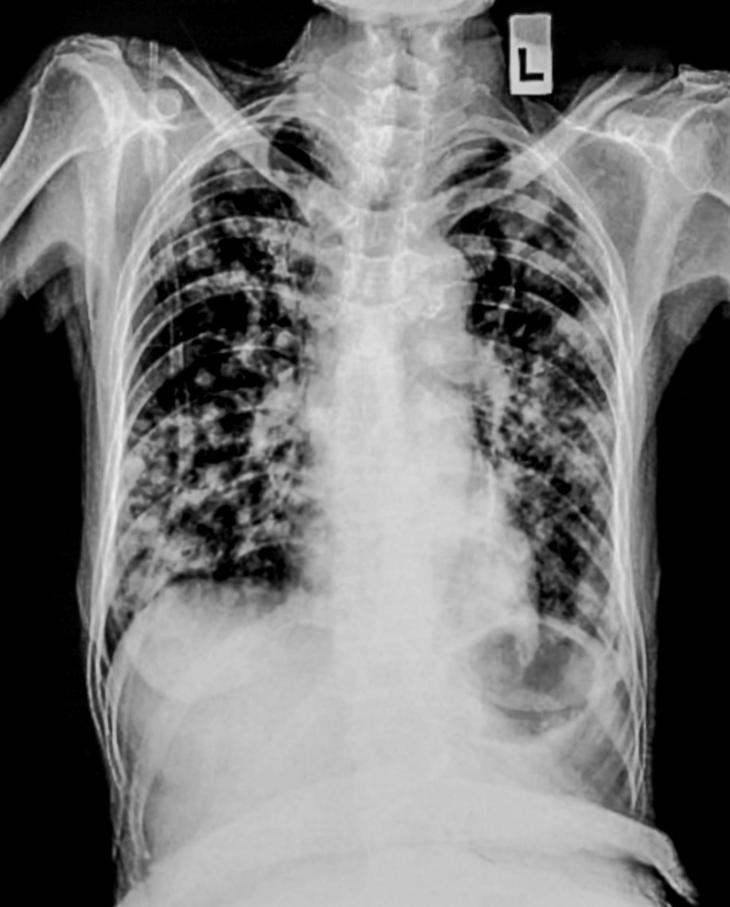

A pesar de los avances en medicina, la tuberculosis sigue siendo una de las enfermedades infecciosas más letales del mundo. Cada día, miles de personas mueren por causas asociadas a esta patología, especialmente en países de ingresos bajos y medios donde el acceso al sistema de salud es limitado.

El problema se agrava con la aparición de cepas resistentes a los medicamentos, lo que complica los tratamientos y eleva los costos sanitarios. Esta situación evidencia la necesidad de fortalecer los sistemas de salud y garantizar diagnósticos tempranos y tratamientos adecuados.